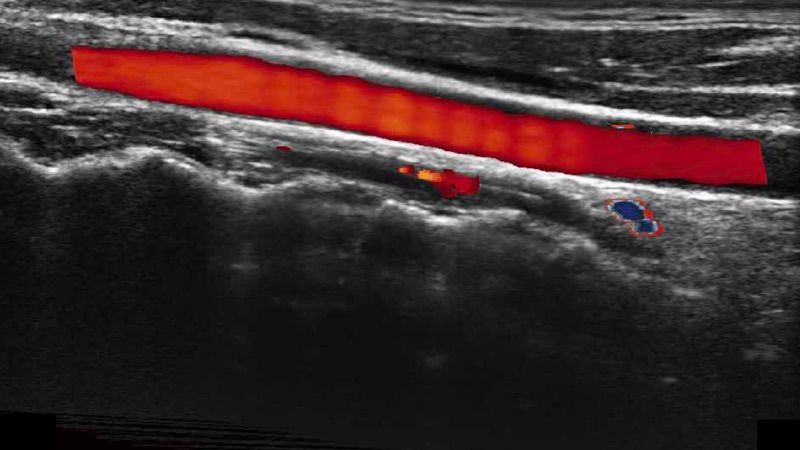

凸陣、線陣和相控陣探頭進(jìn)行實(shí)時(shí)掃描時(shí),開啟擴(kuò)展成像模式,可以擴(kuò)展超聲圖像視野,以便更完整地查看大的病灶或組織器官的解剖結(jié)構(gòu)。

通過色彩血流和實(shí)時(shí)寬景相結(jié)合,可觀察到完整的靜脈或動(dòng)脈的血流,方便醫(yī)生檢查。實(shí)時(shí)掃查過程中,如有任何操作失誤也可以很容易地進(jìn)行回掃擦除,而不會(huì)中斷掃查。